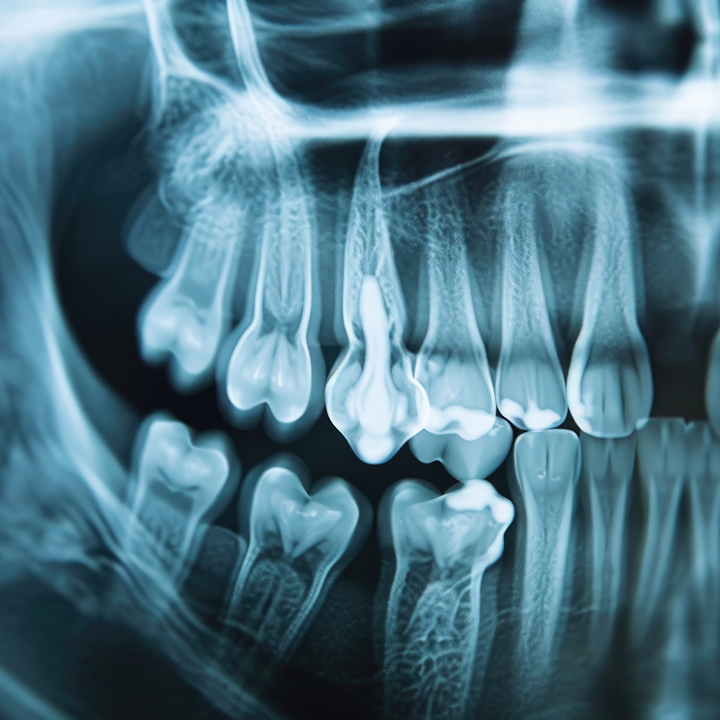

Radiographie panoramique

La radiographie panoramique offre une vue d’ensemble complète de la bouche : dents, mâchoires, sinus, articulations temporo-mandibulaires et structures voisines. Elle est essentielle pour détecter des pathologies invisibles à l’œil nu comme des dents incluses, kystes, infections ou anomalies osseuses. Non invasive et rapide, elle permet un diagnostic global en une seule prise.

Cette technologie est précieuse dans la préparation de traitements implantaires, orthodontiques ou chirurgicaux. Elle améliore la sécurité des soins en permettant une évaluation précise et complète des structures dento-faciales.